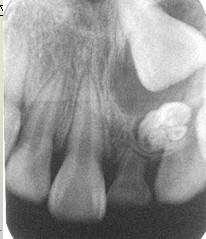

恒牙早萌病因:乳牙根尖周炎,局部因素:乳牙早失--牙龈组织致密;牙龈纤维瘤病,萌出性囊肿,埋伏多生牙,乳牙萌出过迟:1岁萌出,3岁出齐,个别牙迟萌少见,多数牙迟萌与全身因素有关。恒牙萌出迟缓:个别乳牙根尖周病变,早失或滞留。牙齿迟萌的治疗包括:开窗助萌、摘除牙瘤、额外牙或囊肿,牵引复位。

牙齿异位萌出的临床表现包括:第一恒磨牙近中边缘嵴阻生于第二乳磨牙远中牙颈下,X线:第二乳磨牙远中根牙颈部吸收区或非典型性吸收,第一恒磨牙近中边缘嵴嵌入;第二乳磨牙间隙开始缩小。治疗措施包括:早期临床观察,钢丝结扎分离,截冠加金属冠修复,拔除第二乳磨牙,导萌器引导恒牙萌出。